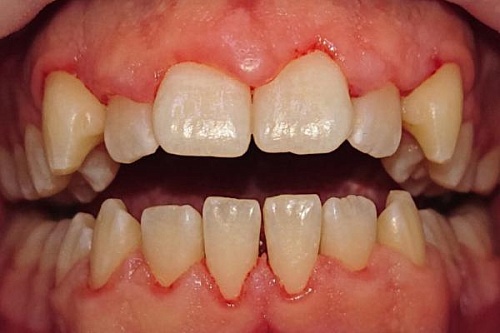

Снятие твердых зубных отложений ультразвуком

Удаление твердых зубных отложений ультразвуковой насадкой у девушки 27 лет.

Снятие твердых зубных отложений ультразвуком До

Снятие твердых зубных отложений ультразвуком После